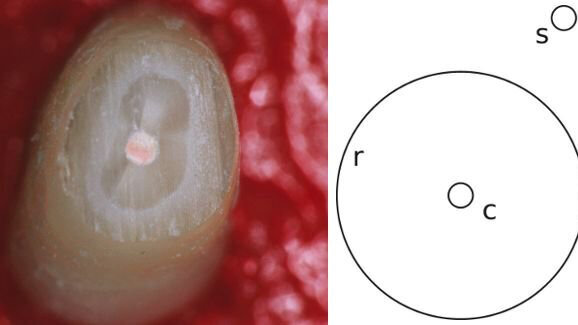

Tijdens klinische tests behandelden acht tandarts-endodontologen uit Nieuw-Zeeland elk meer dan twintig geëxtraheerde elementen met een gevuld wortelkanaal. De participanten werd gevraagd zo min mogelijk weefsel weg te halen bij het prepareren van de elementen en om gebruik te maken van hun gebruikelijke handinstrumenten. De onderzoekers constateerden dat de tandartsen ten prooi vielen aan de Delboeuf-illusie, die inhoudt dat begrensde kleine gebieden kleiner lijken in een grotere context. In dit geval leek een geboorde caviteit kleiner als het omringende weefsel in het bereik van de parameters van de illusie lag. Als gevolg werd meer gezond weefsel dan nodig verwijderd.

De Delboeuf-illusie is genoemd naar de Belgische wetenschapper Joseph Remi Leopold Delboeuf en dateert uit 1865. De Delboeuf-illusie wordt regelmatig toegepast door restaurants: door kleinere borden te plaatsen op een groter bord, lijkt het volume van het kleine bord relatief klein en denkt de klant dat hij meer moet bestellen.